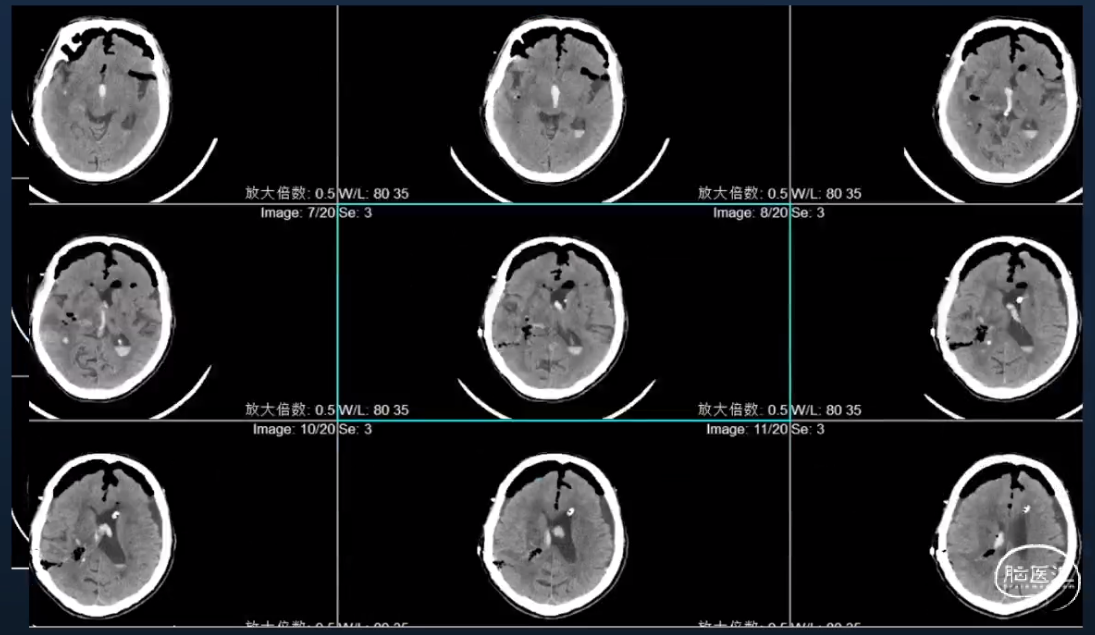

本文主要从基底节出血经眉弓额极入路、丘脑出血手术入路两个部分,多角度分享脑出血内镜手术与技巧。